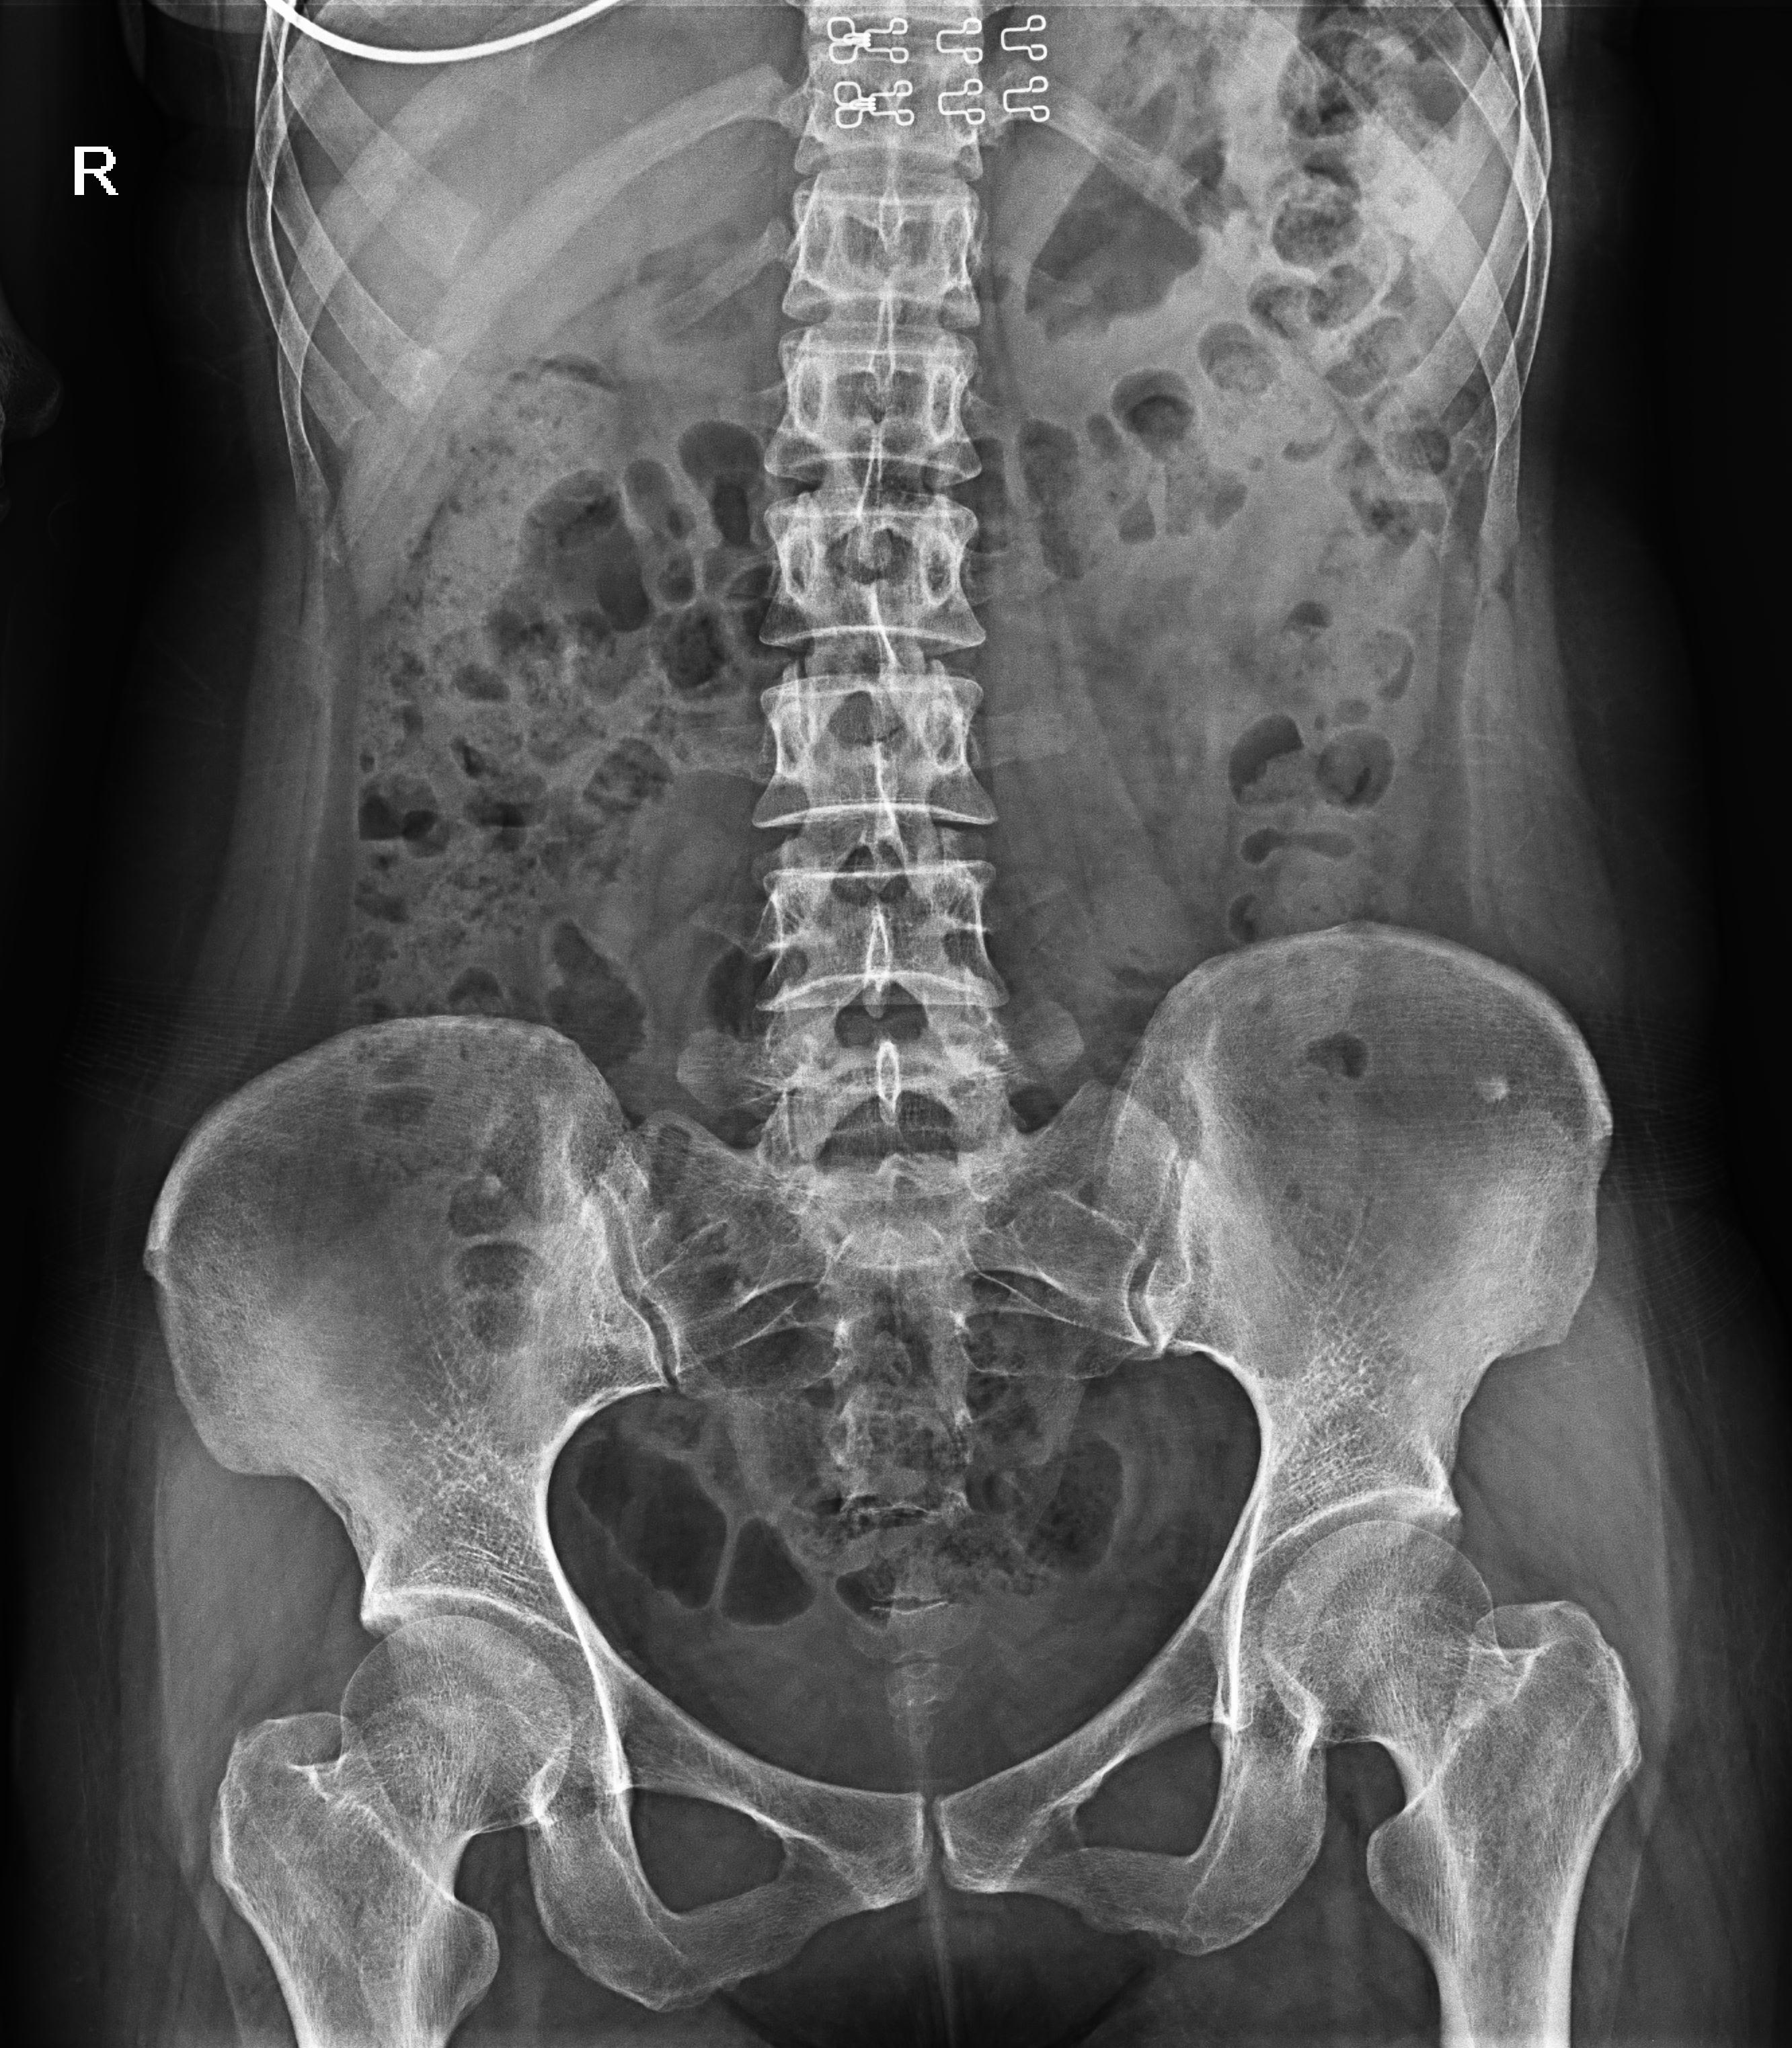

普利德醫(yī)療自主研發(fā)的新一代數(shù)字化X線透視攝影系統(tǒng),可應用于DR攝影、數(shù)字透視、數(shù)字造影以及可視化精準DR拍片等多種臨床X線檢查領域。

球管傾斜攝影角度-45°~45°,滿足臨床各部位各角度的攝影需求。如:髕骨軸位、頸椎正位、骶尾椎、鼻竇瓦氏位、梅氏位等部位檢查。

點片裝置移動范圍大,無需患者移動就能完成全身各部位的檢查;